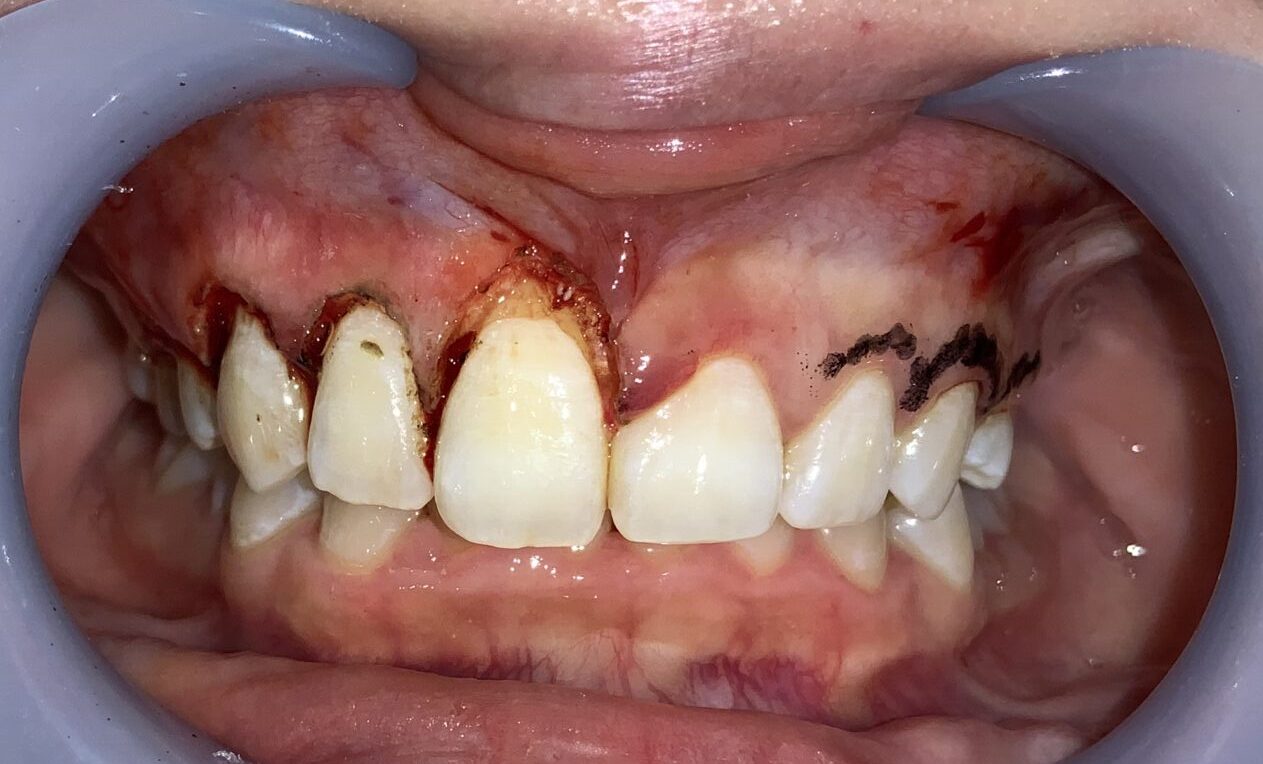

まずは1本だけ歯冠長延長術を行い、切除範囲や歯の大きさ、歯ぐきの長さ、歯と歯ぐきのマッチングを患者様に確認をして頂きます。

1本だけですが、このように違いがわかります。特にこの歯は、歯槽骨がとがっていたので、歯槽骨整形も同時に行いました。追加の費用はありません。

向かって左側(患者様の右側)を全て整えました。

左右の差がはっきりとわかります。